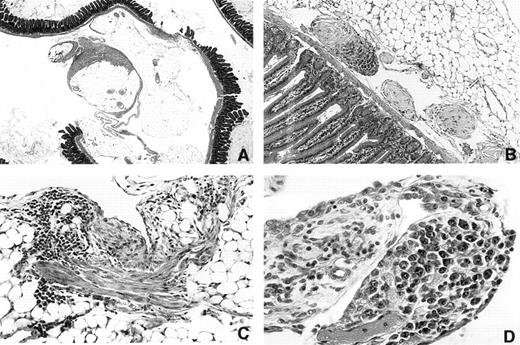

Inhibition of plastic disc induced PCT formation by INDO.When it was clear that mice could be maintained on INDO in the drinking water for more than 300 days, it became possible to determine if INDO could inhibit induction by plastic discs. This was of special interest because on-going histological studies of mice bearing i.p. discs indicated that this kind of foreign body produced a very different pathological response than was seen with oils. Essentially, there was no accumulative granuloma deposition on mesenteric surfaces, but instead the discs induced a patchy fibroplastic reaction (Fig 4A and C) that varied in amount from mouse to mouse. Occasional polyp-like structures containing collagenous material was seen near the mesenteric attachment sites (Fig 4B). The omentum was frequently adherent to the disc and appeared thickened. Most plastic discs were found to be adherent to the peritoneal connective tissues of the abdominal wall or omentum. An occasional disc was found in the retroperitoneum. In a few mice the disc was unattached. Varying numbers of adhesions of disc to intestine, omentum, abdominal fat, or abdominal wall were found. The discs themselves were also covered by a tenacious fibrous capsule. Adhesions of the discs to the omentum often contained blood vessels. It was suspected that in some of the mice this connective tissue bridge was broken as the surfaces of some of the disc contained piled-up necrotic tissue. The PCTs, however, did not appear to develop in the dense fibroplastic tissue as they were found either in the omental connective tisues (Fig 4D) or were first detected as multiple growths attached to or within small fibrotic polyp-like structures (Fig 4B).

Photomicrographs of peritoneal surfaces in mice carrying Lucite 21× 2 mm plastic discs. (A) 3616 1.5 × 2× Day 315. Section through mesenteric fat and intestine showing patchy fibrous deposition on mesothelial surfaces of mesenteric fat. Note that much of the surface is not covered. (B) 3173 20 × 10× Day 214. Region near the mesenteric attachment site containing three polyp-like structures. The two light staining polyps contain fibrinoid tissue covered with mesothelium. The third polyp is invaded by plasmacytoma cells. (C) 3164 20 × 5× Day 214. A patch of fibrous tissue on a fat surface on the left. The tissue contains numerous lymphocytes. (D) 3333 20 × 5× Day 258 Vascularized polyp-like structure arising from the omentum that contains a focus of atypical plasma cells. This was the only plasma cell lesion found in this mouse.

Accordingly, 23 C.D2 I/P control mice were implanted with 21 × 2-mm Lucite discs and another 23 were given discs and treated continuously with 20 μg/mL INDO in the drinking water. By day 289, seven of the controls had developed PCTs that were diagnosed by cytofuge smears and confirmed histologically. At day 361 two more controls developed PCTs bringing the total incidence to 39%. Of the 23 mice given INDO continuously, 7 were autopsied at day 361 to 3633 and 15 were autopsied and examined histologically between days 393 and 397, and no PCTs were found.